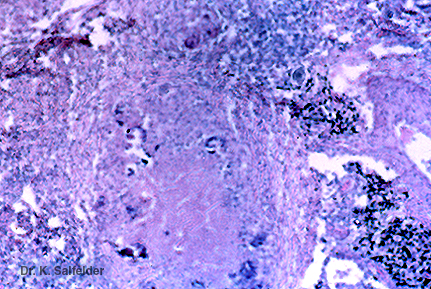

Abb. 17,19: Pneumozystose

In den nekrotischen Tumormassen (Abb. 17,17 und 17,18) finden sich auch Verkalkungen. HE-Faerbung